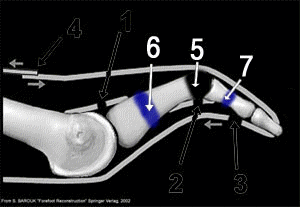

Le patient se plaint de douleurs plantaires (métatarsagies) mais aussi dorsales. L'orteil apparait en griffe et il se produit peu à peu une luxation métatarso-phalangienne dorsale (le deuxième orteil est spontanément relevé par rapport aux autres, voire complètement luxé lorsque se rompt la plaque plantaire, renforcement qui stabilise l'articulation).

....une ostéotomie du deuxième métatarsien, selon la technique de Weil, souvent étendue au métatarsien adjacent voire aux autres métatarsiens latéraux selon leur forme et leur longueur, de façon à conserver une courbe harmonieuse.

Le but de cette ostéotomie et de corriger les troubles d'appui par un raccourcissement du métatarsien...

schémas confiés par S. Barouk